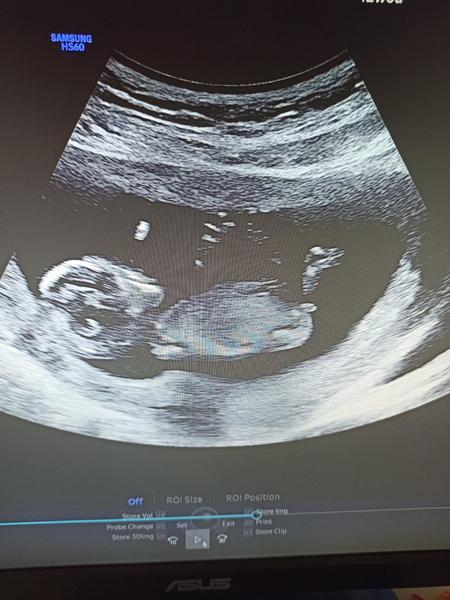

Holky, já se z dovolením přidám. Co by jste si troufly rici, že to je chlapecek nebo holcicika? Doktorka na screeningu rikala na 70% kluk. Mam doma už dva, a prostě vůbec se mi tomu nechce věřit, že se té holčičky už nedočkam 😞😀🙏🏻🙏🏻 Kazdopadne jsme radi, ze je miminko zdrave 🩵🙏🏻